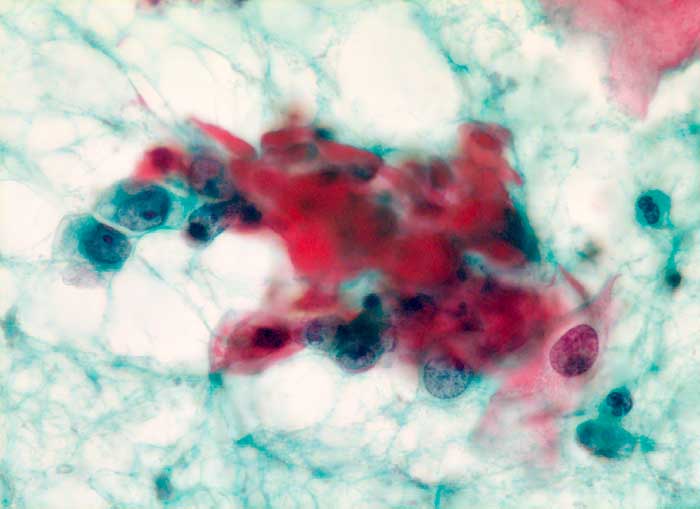

Die Tumorzellen liegen einzeln oder in kleinen Verbänden und ganzen Gewebsfragmenten. Die polymorphen Kerne sind vergrössert und enthalten verklumptes unregelmässig verteiltes Chromatin und grosse Nukleolen. Gut differenzierte Karzinome erkennt man am breiten und oft verhornten Zytoplasma. Längliche bis fadenförmige Tumorzellen mit pyknotischen Kernen können als einziger Hinweis auf das Vorliegen eines Karzinoms vorhanden sein. Wenig differenzierte Karzinome haben polymorphe und schlechter erhaltene Kerne. Der Hintergrund ist meist detritisch und oft hämorrhagisch. Ulzeration, Einblutungen und bakterielle Infektionen beeinflussen den Erhaltungszustand und die Art der abgestrichenen Zellen. Ist die Oberfläche eines ulzerierten Karzinoms von einem Fibrinschorf bedeckt, enthalten die Ausstriche lediglich Detritus, Granulozyten und Erythrozyten, aber keine Tumorzellen. Die Sensitivität für die Karzinomdiagnose ist aus diesem Grund geringer als für die Diagnose eines Carcinoma in situ.